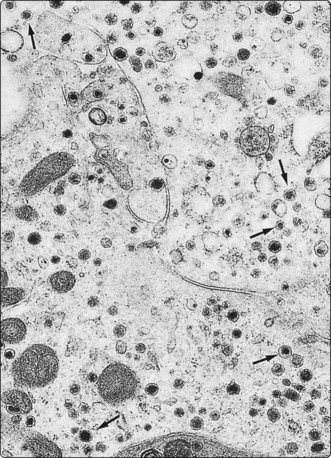

Electron microscopy32-38

Although immunocytochemistry has become the most important ancillary method for tumor subtyping, we still find EM necessary for some cases. EM is particularly useful in unusual lung or mediastinal lesions. In Silverman’s experience, FNB samples are the most frequent non-renal samples sent for EM.

We decide on cases to be further studied after an initial evaluation of material in the radiology theater. The most commonly used method of fixation is to eject the aspirate into a small test tube containing glutaraldehyde. Many methods of processing tissue are suggested, mainly with the aim of separating tumor tissue from contaminating red cells. We use Lazaro’s method of cell concentration. The small pellet produced by centrifugation is carefully removed and processed.39 For highly cellular aspirates, the material can be ejected as a semisolid droplet onto a carefully cleaned slide, which is then immersed in glutaraldehyde (compare cell ‘buttons’ as described above). The droplet can be processed on the slide or popped off for further handling. A report can be given in 24–48 hours if necessary.

There is evidence for representative sampling and superior fixation of FNB material compared with surgically excised material (Figs 2.20-2.22).24 In a review of 150 of our cases from various sites, 100 contained adequate well-preserved material for assessment. In 60% of these cases EM only confirmed the LM diagnosis, but in 40% the findings were diagnostic per se. The common applications of EM in FNAC are summarized in Table 2.3. In our experience, most value is obtained in recognizing neuroendocrine tumors and in the specific diagnosis of melanoma, mesothelioma and some carcinomas, including metastases, where immunocytochemistry often cannot provide such positive diagnostic features. An expanding literature about techniques and applications is available.

image

Fig. 2.20 Resin-embedded tissue fragment for EM

Fragment of sarcoma obtained with a standard 22-gauge needle, fixed in glutaraldehyde and processed on the slide, 1 µm section (Toluidin blue, HP).

Fig. 2.21 Electron microscopy – carcinoid tumor

FNB of metastatic neoplasm in the liver. Numerous intracytoplasmic rounded neurosecretory granules averaging 155 nm in diameter. In some, a submembranous lucent halo is seen (arrows) (EM × 13 650).